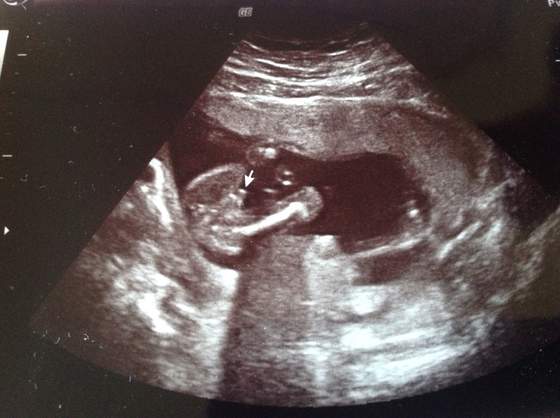

u Verity mozliwa dziewczynka wiec reszta dziewczyn ciekawe co u Was? Jakies preferencje?

Verita, powodzenia jutro! Bedzie dobrze! Trzymam kciuki baw sie dobrze i bierz z kazdej chwili co najlepsze dla Ciebie!!! Licze na sprawozdanie!!!